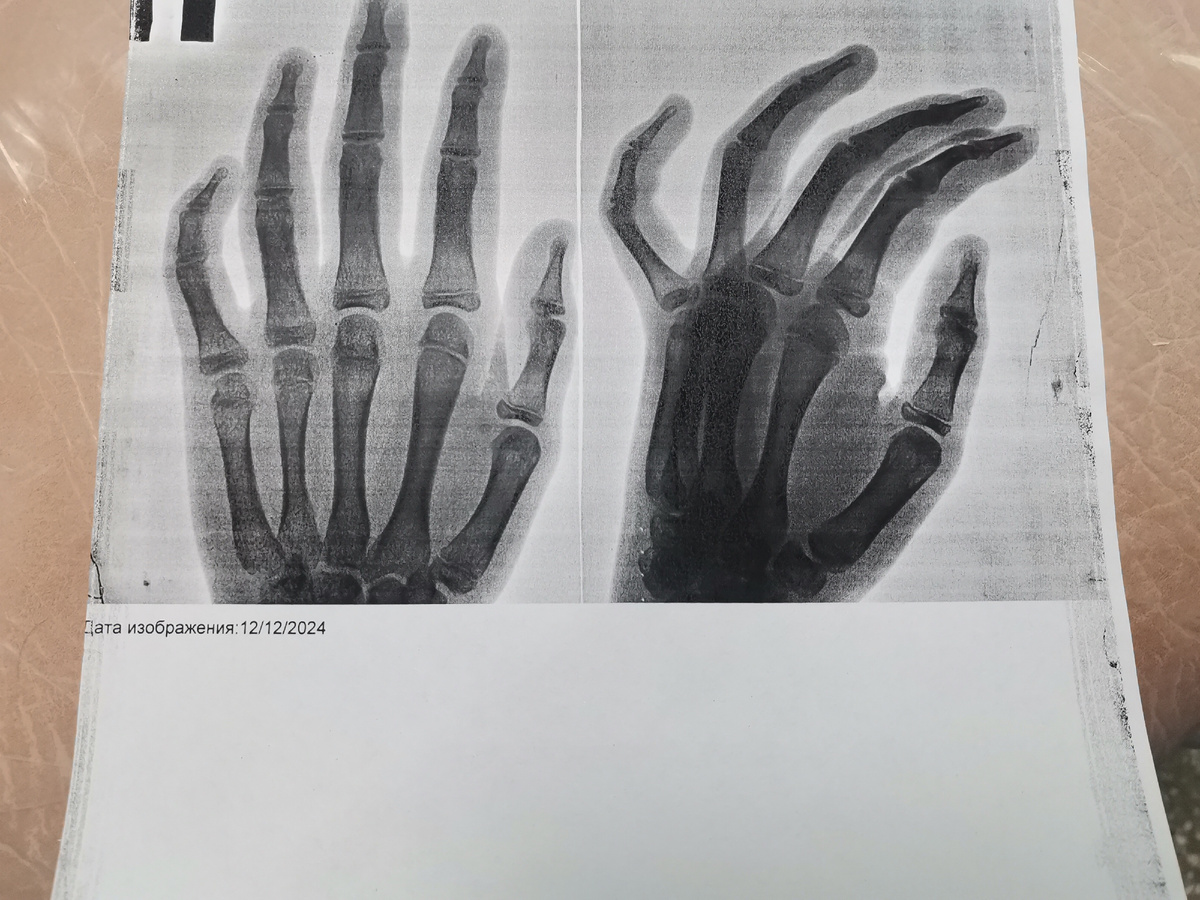

Только вот мое утро началось в травмпункте. Позвонили с лицея. Мирослава на физкультуре травмировала кисть руки. Мячик прилетел.

Забрала плачущего ребенка с распухшим пальцем на правой руке и поехали на снимок.

Хорошо, что приняли во взрослой поликлинике, и не пришлось ехать в другую часть города.

Перелома нет. Только ушиб.

Кости целы